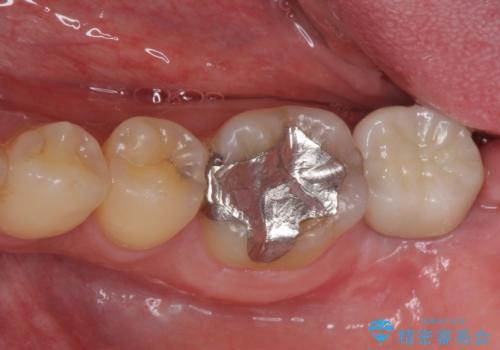

抜歯してからインプラント埋入までには時間がかかるため、その間に下顎左右臼歯の金属のブリッジをオールセラミックへ変えていくこととしました。

目立つ部分の銀歯や気になる変色歯をまとめてきれいに仕上げることができました。